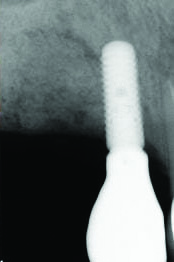

Fig 1 and Fig 2. Case 1: Initial clinical presentation with gutta-percha placed in the apical fistula of tooth No. 9 (Fig 1); radiograph showing gutta-percha point leading to the periapical lesion (Fig 2).

Patient 1: A 30-year-old female patient with an unremarkable medical history presented with implant No. 9 exhibiting retrograde peri-implantitis. Tooth No. 9 had been replaced with the implant 8 years prior because of a history of trauma and failed root canal treatment. The implant exhibited a periapical radiolucency with the sinus tract tracing to the apex of implant No. 9 (Figure 1 and Figure 2). The patient had a high smile line with longer clinical crowns at Nos. 9 and 10 compared with Nos. 7 and 8 (Figure 1 and Figure 2).